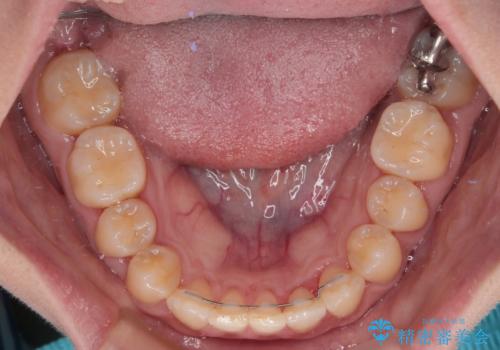

- 矯正装置

- メタルブラケット

- 治療期間

- 8ヶ月

このような咬み合わせの方の多くは、舌の突出癖が強い傾向にあり、反対咬合改善後に開咬となってしまい、なかなか治療が終わらないことがあります。

こちらの患者様は、舌のトレーニングを治療開始前から徹底的に実践していただき、僅か8ヶ月という短期間で治療を終えることができました。